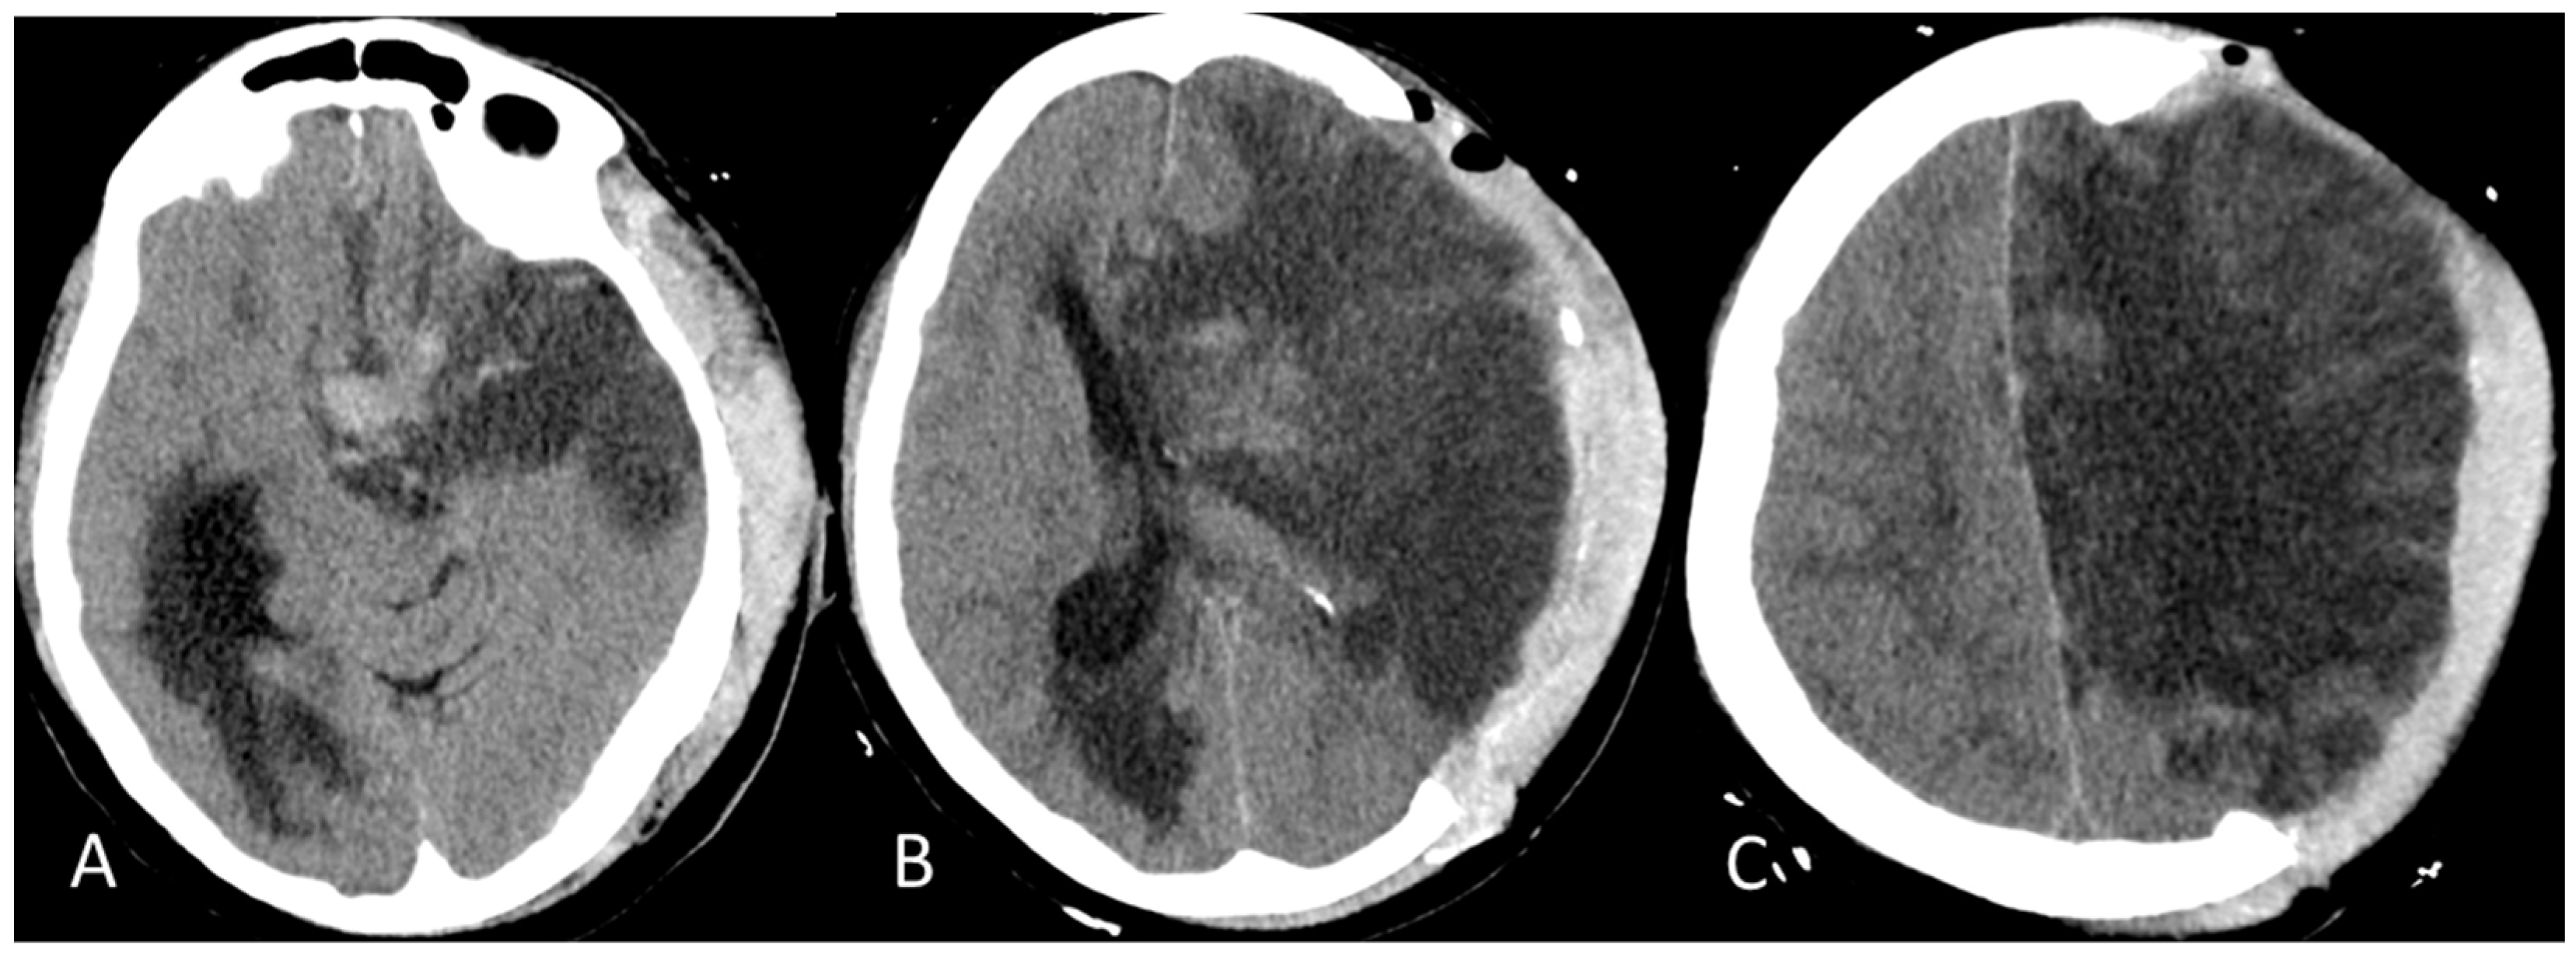

2. Detailed Case Description